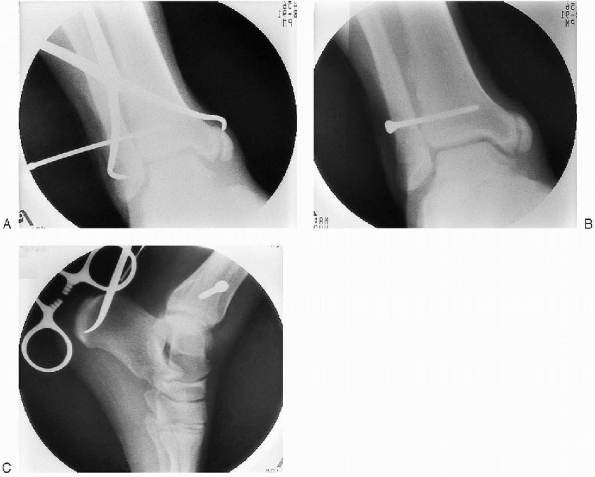

![]()  |

FIGURE 33-24. A to C: Stabilization of the syndesmosis using a fully threaded, 3.5-mm cortical screw placed through three cortices.